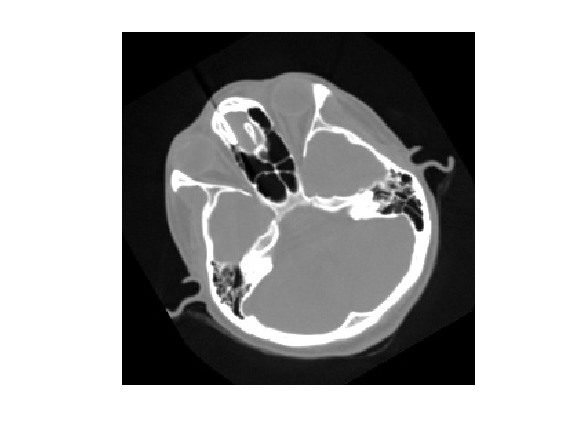

Let's call an itk filter and look at the result.

pyrun(["smoothed = itk.discrete_gaussian_image_filter(image, sigma=sigma)"], sigma=3.0);

smoothed = pyrun(["smoothed = itk.dict_from_image(smoothed)"], "smoothed");

imshow(uint8(smoothed{"data"}))